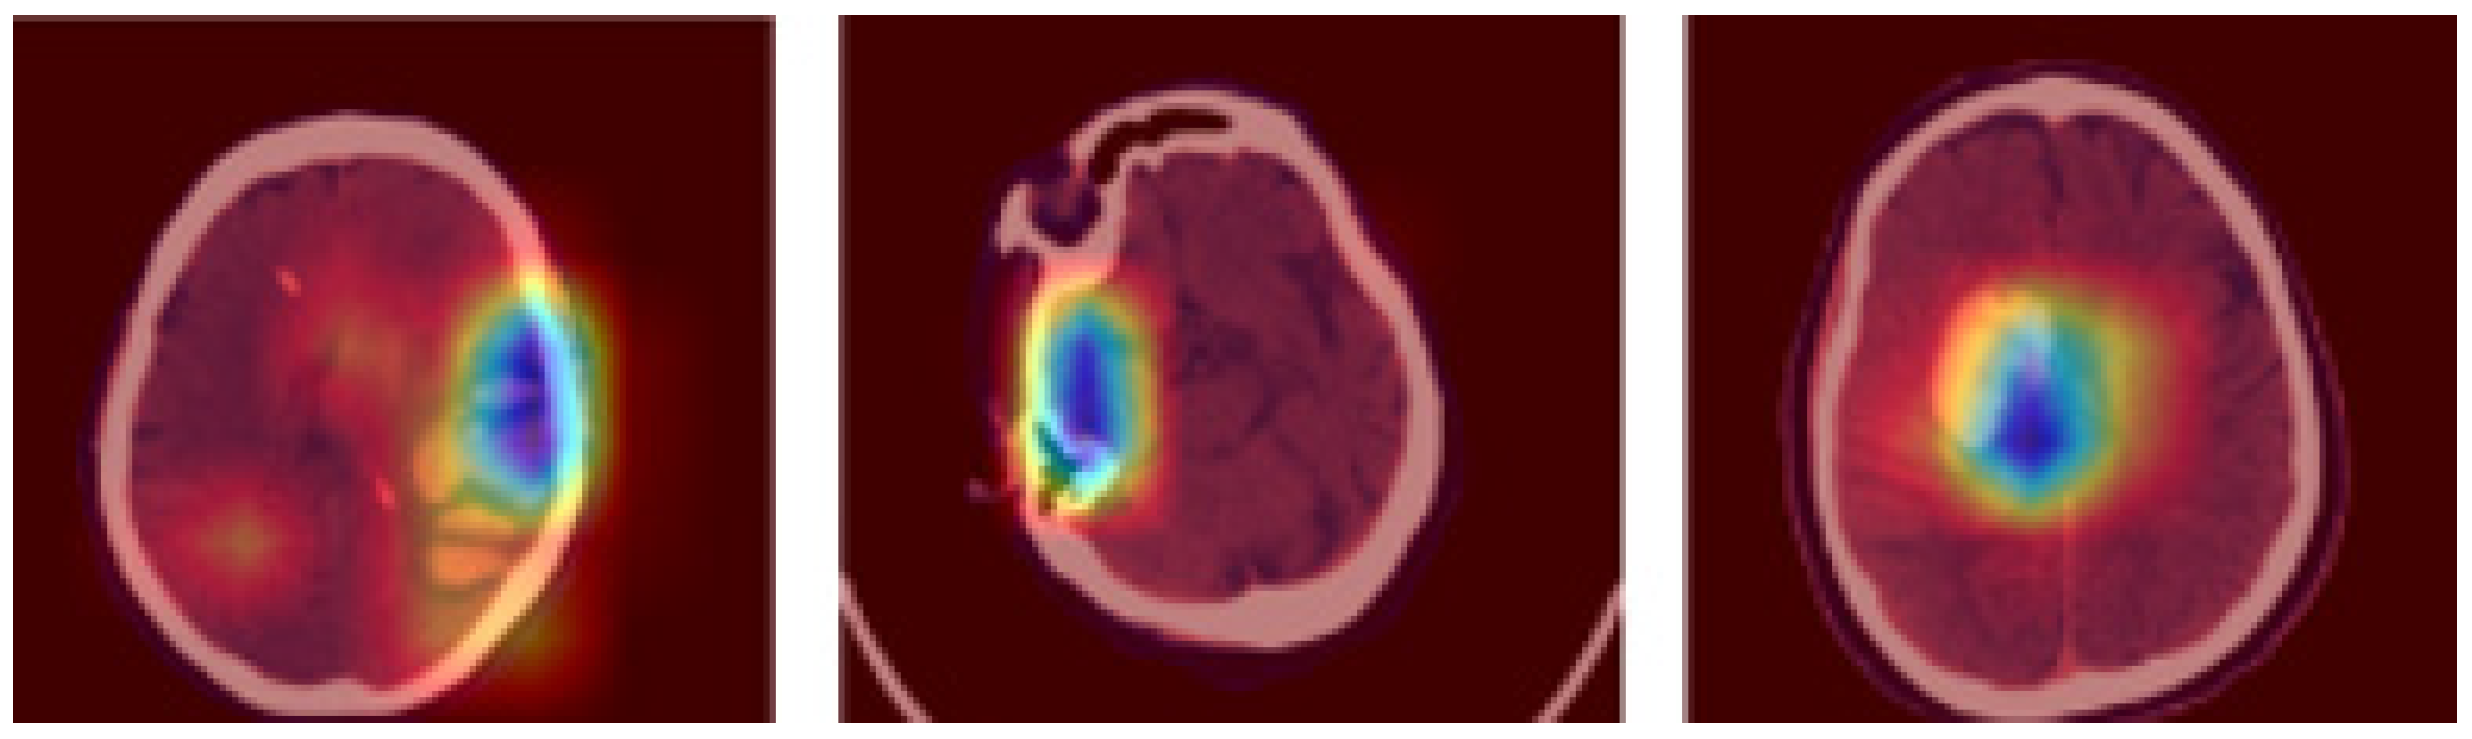

3.2. Image Segmentation